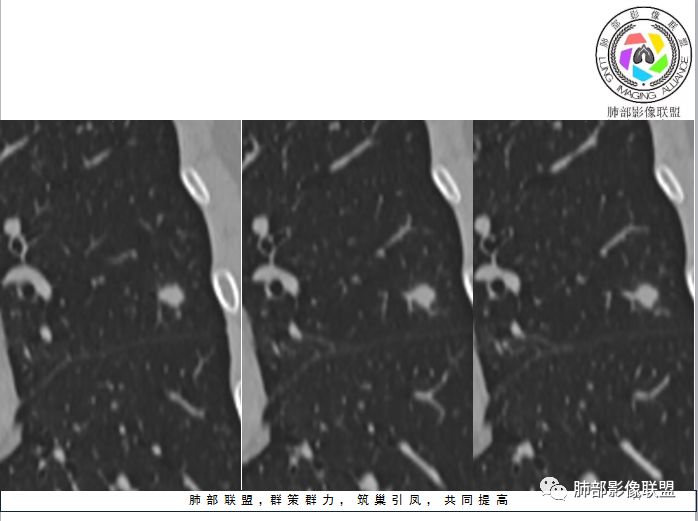

1、与炎性假瘤、恶性肿瘤鉴别:恶性肿瘤边缘膨隆,收缩也是毛毛糙糙的,炎性假瘤收缩力较强,边缘凹陷的多。隐球菌孤立结节收缩力弱,膨胀力也弱,与胸膜关系多为糊墙,部分有间隙。右边两幅可以看到胸膜增厚,胸膜下脂肪间隙增宽。晕中长毛刺,边缘平直,血管走行自然,鉴别肺癌。

3、与淋巴结鉴别:淋巴结小于1cm,多位于胸膜下。结节周围不应该有晕,可以与血管相连,与胸膜有多条影相连

4、与曲霉鉴别:曲霉少见孤立性病灶,除非寄生性的。出现长毛刺和晕则往往见于免疫力下降病例。曲霉不强化。血管炎孤立的少,一般是多态多灶,周围长索条,一般是包膜样强化。